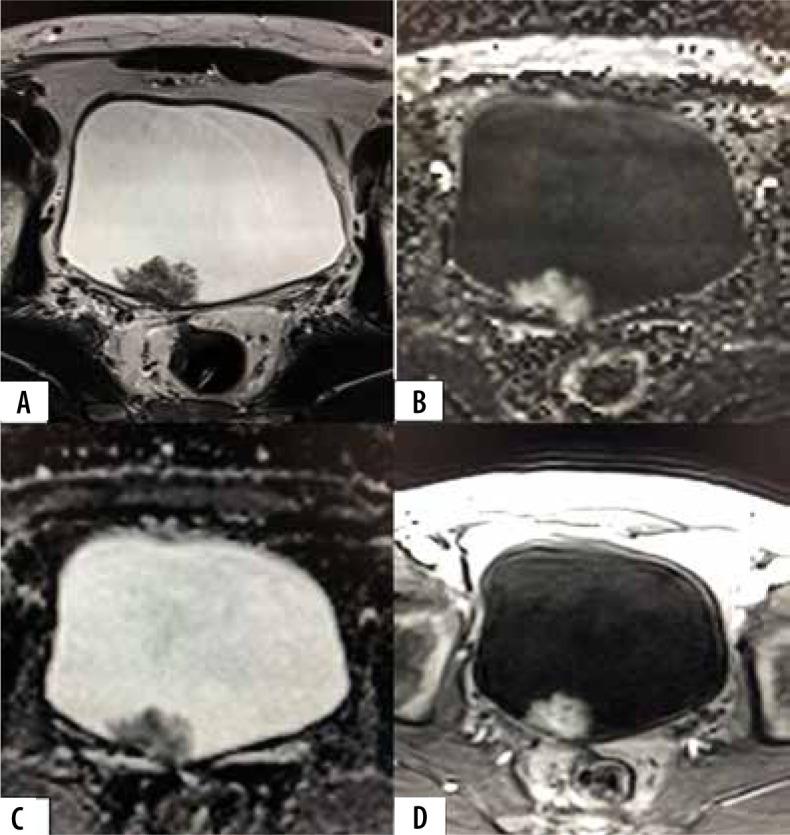

The purpose of the present study was to assess the diagnostic accuracy of the Vesical Imaging-Reporting and Data System (VI-RADS) scoring system in predicting muscle infiltration of bladder cancer (BC) on a pre-operative multiparametric magnetic resonance imaging (mpMRI).

The prospective study enrolled patients with bladder lesions detected on a preliminary ultrasonography or cystoscopy. The patients underwent mpMRI on a 3T MRI scanner followed by surgery within 2 weeks. The tumours were assigned a VI-RADS score by 2 experienced abdominal radiologists. The VI-RADS score was compared with postoperative histopathological findings to confirm detrusor muscle infiltration. The diagnostic performance of VI-RADS for predicting muscle invasion was assessed by calculating sensitivity, specificity, positive predictive value (PPV), negative predictive value (NPV) and accuracy.

A total of 60 patients were included in the study with a male: female ratio of 4.4 : 1. Transurethral resection of bladder tumour (TURBT) was performed in 47 (78.4%) and radical cystectomy in 13 (21.6%) patients. 19 (31.7%) had non-muscle invasive invasive BC (NMIBCa) and 41 (68.3%) had muscle invasive BC (MIBCa) on histopathology. There was a significant association between VI-RADS score and its components with muscle invasion ( < 0.05). A VI-RADS score of ≥ 3 had a sensitivity of 97.56% (95% CI: 0.87-0.99%), specificity of 73.68% (95% CI: 0.49-0.91), positive predictive value of 88.9% (95% CI: 0.79-0.94), negative predictive value of 93.33% (95% CI: 0.66-0.99), and diagnostic accuracy of 90% (95% CI: 0.80-0.96) for prediction of muscle invasion.

VI-RADS scoring system pre-operatively predicts the likelihood of muscle invasion in BC with a satisfactory diagnostic performance, and it should be incorporated in the diagnostic work-up of BC patients.